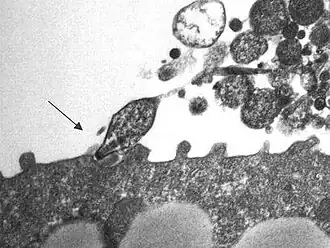

Mycoplasma pneumoniae (лат.) — вид бактерий рода Mycoplasma. Как и все бактерии этого рода, M. pneumoniae — мелкие микроорганизмы (0,3—0,8 мкм), не имеющие жёсткой клеточной стенки (в результате чего от внешней среды их отделяет лишь цитоплазматическая мембрана) и c ярко выраженным полиморфизмом. Строгий аэроб.